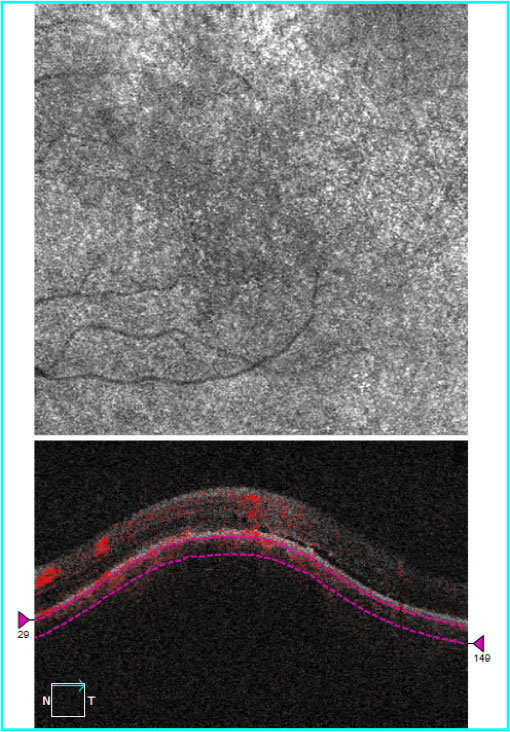

The OCT image through the lesion demonstrates bowing of the RPE over the underlying choroidal mass. A small amount of subretinal fluid is also noted. The OCT-Angiogram demonstrates some increased vascularity but in isolation could not be used for diagnostic confirmation.

A video file demonstrating the appearance of the lesion on a macular cube scan. Note that the superior aspect captures a small portion of the lesion and the remainder demonstrates subretinal fluid and atrophy inferiorly.